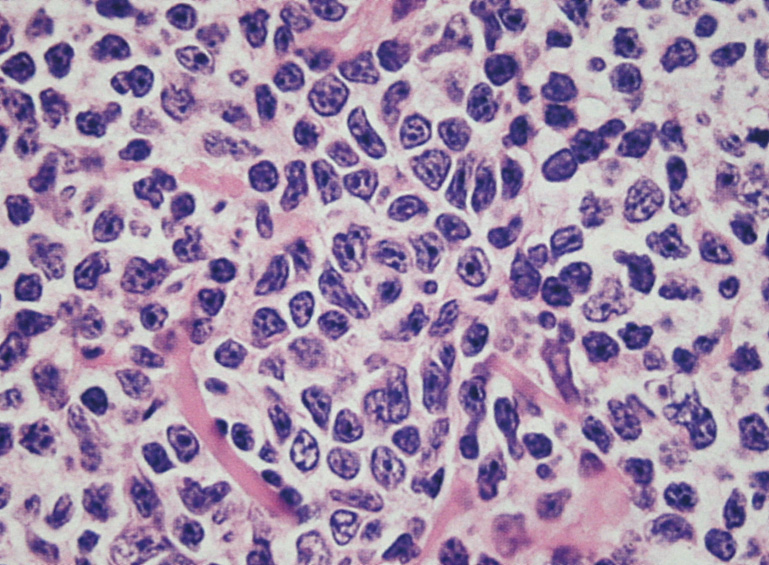

- 典型例はmarginal zoneのcentrocyte-like cellの増殖といわれるが非典型例も多い

- 分化してplasma cell様の形態をとる. Dutcher body(核内偽封入体)など異型所見あり。

- 核不整のほとんどみられないsmall lymphocytic lymphoma/chronic lymphocytic lymphoma cellと同じ形態の細胞が増殖する症例がある.

| centrocyte-like cell | monocytoid cell | plasmacytoid |